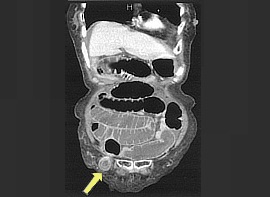

腹痛と嘔吐を主訴に精査加療目的に受診。CT検査にて、右鼡径部にヘルニア及び腸閉塞を認め、精査の結果、大腿ヘルニア嵌頓(かんとん)と診断。徒手整復を試みたが整復できず、手術(腹腔鏡下ヘルニア手術)を施行した。

CT画像